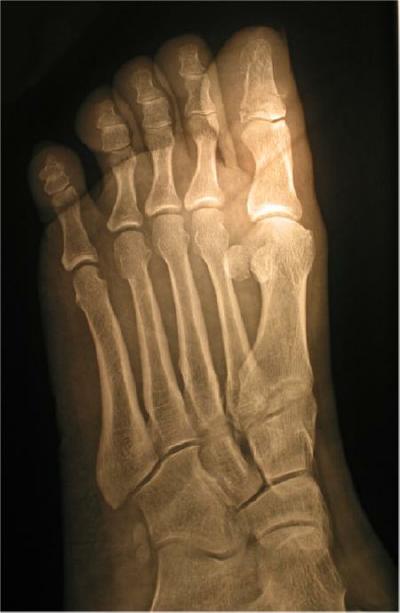

Examination by emergency medical people at a local hospital revealed the diver has a broken toe (comminuted fracture of the left first digital phalange). Basically, the toe was crushed into multiple fragments. Fortunately, this transverse fracture required no pinning or surgery. This type of fracture tends to heal rather well, but this diver missed diving for eight weeks while his body repaired the damage.

The X-rays below of the injury to the diver's left foot show multiple breaks (fine lines) at the in the first bone  (upper right of oblique view) of the big toe

X-Rays of Comminuted Fracture Caused By A Falling Scuba Cylinder

Antero-Posterior View

Enlarged Antero-Posterior View